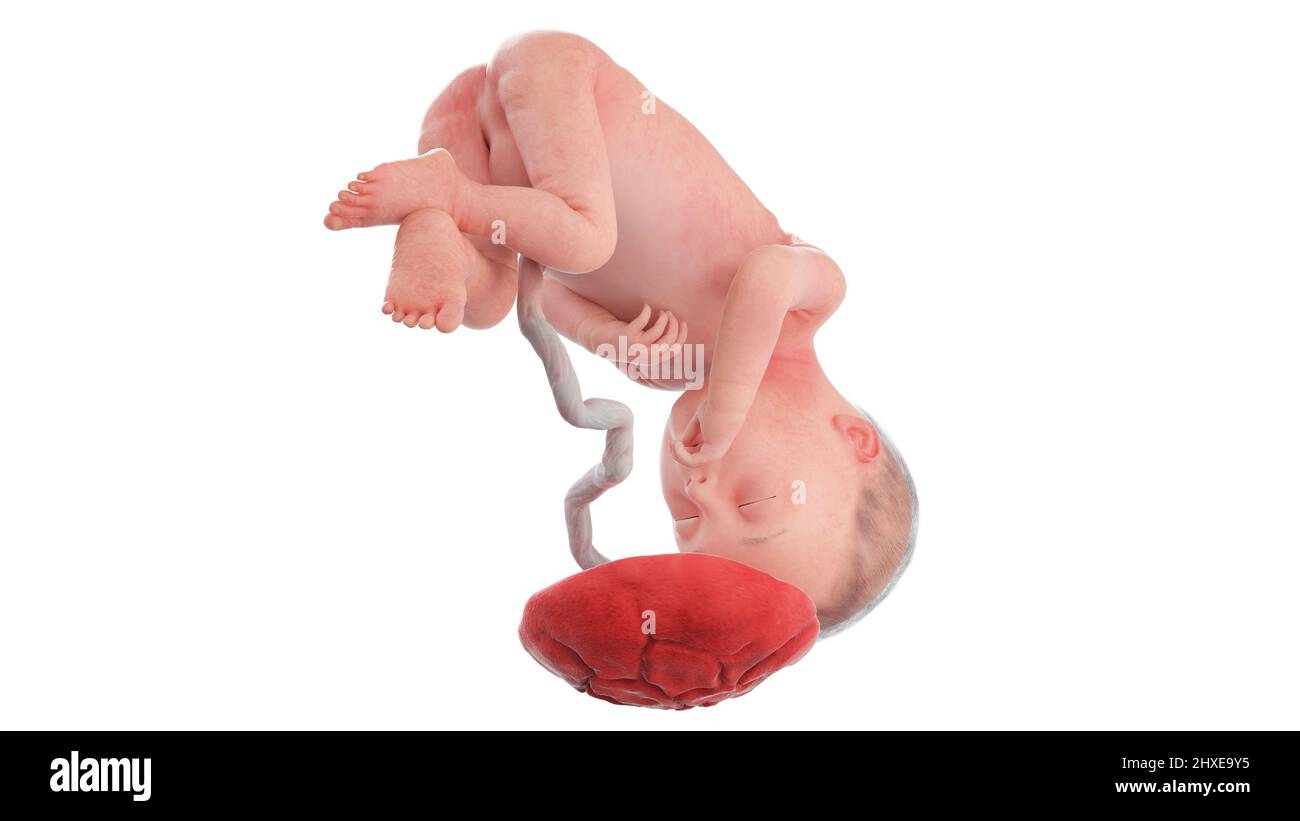

Feto a 27 settimane, artwork Foto Stockhttps://www.alamy.it/image-license-details/?v=1https://www.alamy.it/foto-immagine-feto-a-27-settimane-artwork-52731084.html

Feto a 27 settimane, artwork Foto Stockhttps://www.alamy.it/image-license-details/?v=1https://www.alamy.it/foto-immagine-feto-a-27-settimane-artwork-52731084.htmlRFD1P310–Feto a 27 settimane, artwork

Feto umano età 27 settimane, illustrazione. Foto Stockhttps://www.alamy.it/image-license-details/?v=1https://www.alamy.it/foto-immagine-feto-umano-eta-27-settimane-illustrazione-147221626.html

Feto umano età 27 settimane, illustrazione. Foto Stockhttps://www.alamy.it/image-license-details/?v=1https://www.alamy.it/foto-immagine-feto-umano-eta-27-settimane-illustrazione-147221626.htmlRFJFEEK6–Feto umano età 27 settimane, illustrazione.

Feto umano età 27 settimane, illustrazione. Foto Stockhttps://www.alamy.it/image-license-details/?v=1https://www.alamy.it/foto-immagine-feto-umano-eta-27-settimane-illustrazione-118698396.html

Feto umano età 27 settimane, illustrazione. Foto Stockhttps://www.alamy.it/image-license-details/?v=1https://www.alamy.it/foto-immagine-feto-umano-eta-27-settimane-illustrazione-118698396.htmlRFGW350C–Feto umano età 27 settimane, illustrazione.

Feto umano età 27 settimane, illustrazione. Foto Stockhttps://www.alamy.it/image-license-details/?v=1https://www.alamy.it/foto-immagine-feto-umano-eta-27-settimane-illustrazione-112681659.html

Feto umano età 27 settimane, illustrazione. Foto Stockhttps://www.alamy.it/image-license-details/?v=1https://www.alamy.it/foto-immagine-feto-umano-eta-27-settimane-illustrazione-112681659.htmlRFGF92GY–Feto umano età 27 settimane, illustrazione.

Feto umano età 27 settimane, illustrazione. Foto Stockhttps://www.alamy.it/image-license-details/?v=1https://www.alamy.it/foto-immagine-feto-umano-eta-27-settimane-illustrazione-111973828.html

Feto umano età 27 settimane, illustrazione. Foto Stockhttps://www.alamy.it/image-license-details/?v=1https://www.alamy.it/foto-immagine-feto-umano-eta-27-settimane-illustrazione-111973828.htmlRFGE4RN8–Feto umano età 27 settimane, illustrazione.

Feto umano alla settimana 27, illustrazione Foto Stockhttps://www.alamy.it/image-license-details/?v=1https://www.alamy.it/feto-umano-alla-settimana-27-illustrazione-image463765768.html

Feto umano alla settimana 27, illustrazione Foto Stockhttps://www.alamy.it/image-license-details/?v=1https://www.alamy.it/feto-umano-alla-settimana-27-illustrazione-image463765768.htmlRF2HXE9Y4–Feto umano alla settimana 27, illustrazione

Feto umano alla settimana 27, illustrazione Foto Stockhttps://www.alamy.it/image-license-details/?v=1https://www.alamy.it/feto-umano-alla-settimana-27-illustrazione-image463765769.html

Feto umano alla settimana 27, illustrazione Foto Stockhttps://www.alamy.it/image-license-details/?v=1https://www.alamy.it/feto-umano-alla-settimana-27-illustrazione-image463765769.htmlRF2HXE9Y5–Feto umano alla settimana 27, illustrazione

Feto umano alla settimana 27, illustrazione Foto Stockhttps://www.alamy.it/image-license-details/?v=1https://www.alamy.it/feto-umano-alla-settimana-27-illustrazione-image463765837.html

Feto umano alla settimana 27, illustrazione Foto Stockhttps://www.alamy.it/image-license-details/?v=1https://www.alamy.it/feto-umano-alla-settimana-27-illustrazione-image463765837.htmlRF2HXEA1H–Feto umano alla settimana 27, illustrazione

Feto umano alla settimana 27, illustrazione Foto Stockhttps://www.alamy.it/image-license-details/?v=1https://www.alamy.it/feto-umano-alla-settimana-27-illustrazione-image463765857.html

Feto umano alla settimana 27, illustrazione Foto Stockhttps://www.alamy.it/image-license-details/?v=1https://www.alamy.it/feto-umano-alla-settimana-27-illustrazione-image463765857.htmlRF2HXEA29–Feto umano alla settimana 27, illustrazione

Feto umano alla settimana 27, illustrazione Foto Stockhttps://www.alamy.it/image-license-details/?v=1https://www.alamy.it/feto-umano-alla-settimana-27-illustrazione-image463765740.html

Feto umano alla settimana 27, illustrazione Foto Stockhttps://www.alamy.it/image-license-details/?v=1https://www.alamy.it/feto-umano-alla-settimana-27-illustrazione-image463765740.htmlRF2HXE9X4–Feto umano alla settimana 27, illustrazione

Anatomia del feto umano alla settimana 27, illustrazione Foto Stockhttps://www.alamy.it/image-license-details/?v=1https://www.alamy.it/anatomia-del-feto-umano-alla-settimana-27-illustrazione-image463765847.html

Anatomia del feto umano alla settimana 27, illustrazione Foto Stockhttps://www.alamy.it/image-license-details/?v=1https://www.alamy.it/anatomia-del-feto-umano-alla-settimana-27-illustrazione-image463765847.htmlRF2HXEA1Y–Anatomia del feto umano alla settimana 27, illustrazione

Anatomia del feto umano alla settimana 27, illustrazione Foto Stockhttps://www.alamy.it/image-license-details/?v=1https://www.alamy.it/anatomia-del-feto-umano-alla-settimana-27-illustrazione-image463765833.html

Anatomia del feto umano alla settimana 27, illustrazione Foto Stockhttps://www.alamy.it/image-license-details/?v=1https://www.alamy.it/anatomia-del-feto-umano-alla-settimana-27-illustrazione-image463765833.htmlRF2HXEA1D–Anatomia del feto umano alla settimana 27, illustrazione

Anatomia del feto umano alla settimana 27, illustrazione Foto Stockhttps://www.alamy.it/image-license-details/?v=1https://www.alamy.it/anatomia-del-feto-umano-alla-settimana-27-illustrazione-image463765820.html

Anatomia del feto umano alla settimana 27, illustrazione Foto Stockhttps://www.alamy.it/image-license-details/?v=1https://www.alamy.it/anatomia-del-feto-umano-alla-settimana-27-illustrazione-image463765820.htmlRF2HXEA10–Anatomia del feto umano alla settimana 27, illustrazione

Anatomia del feto umano alla settimana 27, illustrazione Foto Stockhttps://www.alamy.it/image-license-details/?v=1https://www.alamy.it/anatomia-del-feto-umano-alla-settimana-27-illustrazione-image463765855.html

Anatomia del feto umano alla settimana 27, illustrazione Foto Stockhttps://www.alamy.it/image-license-details/?v=1https://www.alamy.it/anatomia-del-feto-umano-alla-settimana-27-illustrazione-image463765855.htmlRF2HXEA27–Anatomia del feto umano alla settimana 27, illustrazione

Anatomia del feto umano alla settimana 27, illustrazione Foto Stockhttps://www.alamy.it/image-license-details/?v=1https://www.alamy.it/anatomia-del-feto-umano-alla-settimana-27-illustrazione-image463765763.html

Anatomia del feto umano alla settimana 27, illustrazione Foto Stockhttps://www.alamy.it/image-license-details/?v=1https://www.alamy.it/anatomia-del-feto-umano-alla-settimana-27-illustrazione-image463765763.htmlRF2HXE9XY–Anatomia del feto umano alla settimana 27, illustrazione